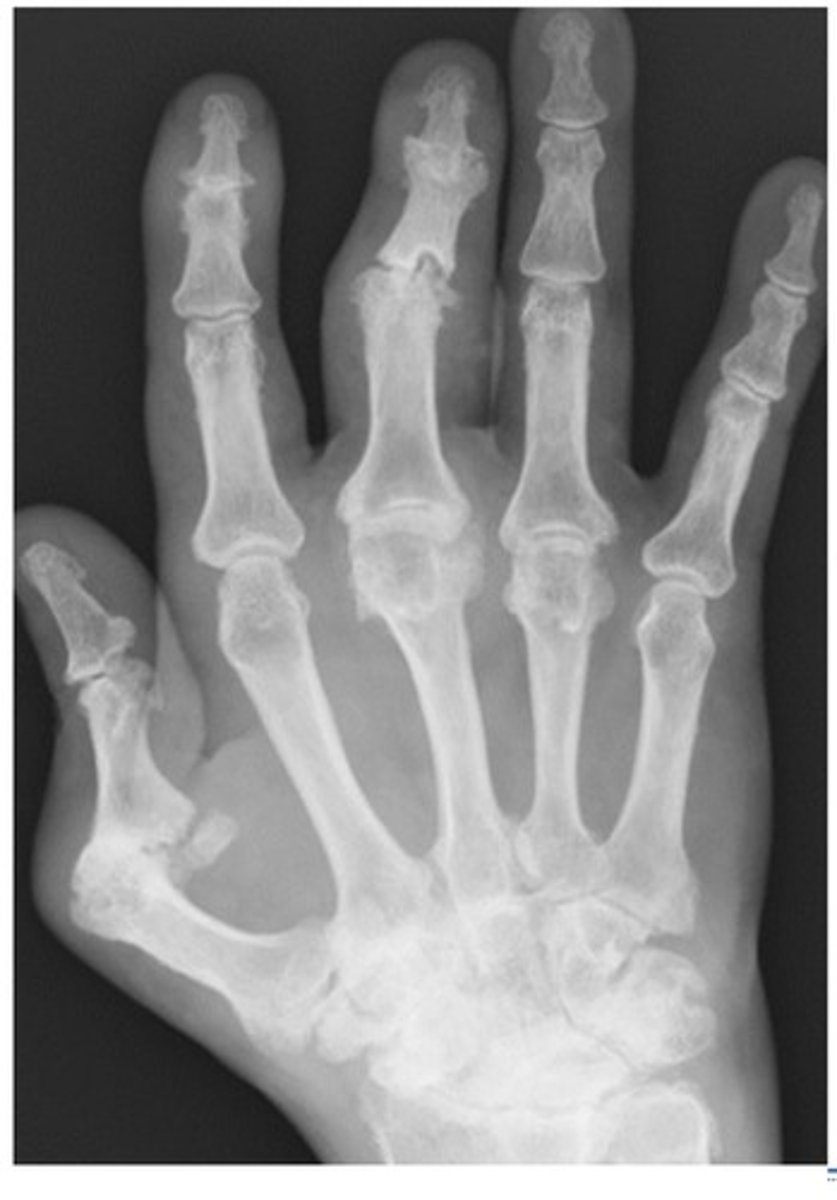

What diagnosis is this?

Enthesopathy ("phyte")